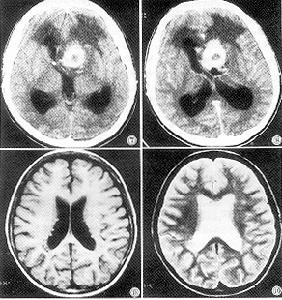

2.CT檢查 第四腦室等或稍高密度占位,部分低密度囊變和鈣化較多見。腫瘤邊界尚清楚易強化,但多不均勻。

3.MRI 多為信號不均勻的長T1長T2病變,呈結節狀矢狀位有利於區分腫瘤與四腦室底小腦蚓部的位置關係和向椎管內伸延的長度(圖1,2)。